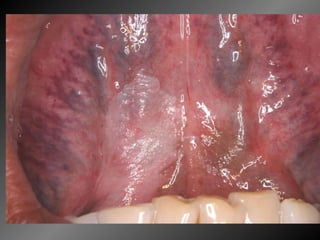

Caso 3

Detalhando... Sexo masculino, melanoderma, solteiro, 45 anos Lesão branca embaixo da língua ,com ardência ao uso de colutório, 10 anos de evolução. Relata uso infreqüente de dipirona para cefaléia. Cirurgias para pterígio e cisto testicular Fumante há 30 anos, 1 maço/dia

Detalhando... Sexo masculino,melanoderma, solteiro, 45 anos Lesão branca embaixo da língua ,com ardência ao uso de colutório, 10 anos de evolução. Relata uso infreqüente de dipirona para cefaléia. Cirurgias para pterígio e cisto testicular Fumante há 30 anos, 1 maço/dia